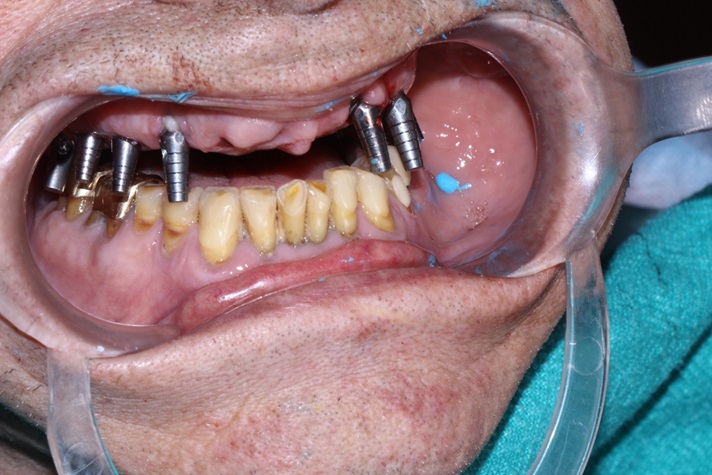

Clinical case image 5 | Implant Screws with Conical connection Chicago IL | Alpha Dent Global

This case report show the successful All on 6 dental implantation using Alpha Dent implants.